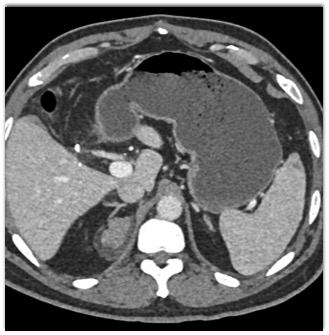

The best diagnosis in this case is

retroperitoneal liposarcoma

retroperitoneal myelolipoma

adrenal hemorrhage

adrenal myelolipoma